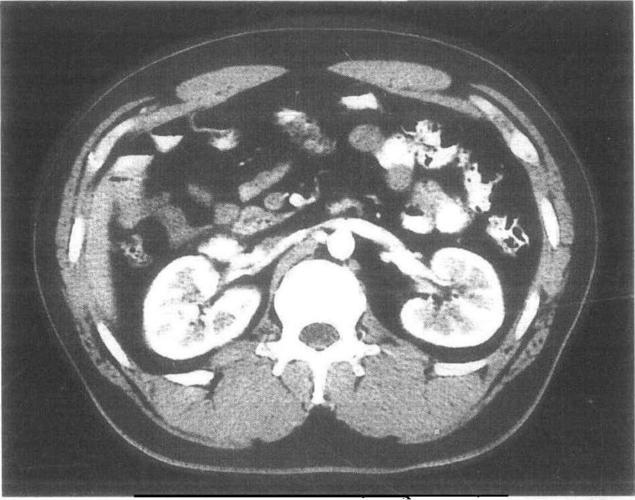

肾脏正常及变异ct图像